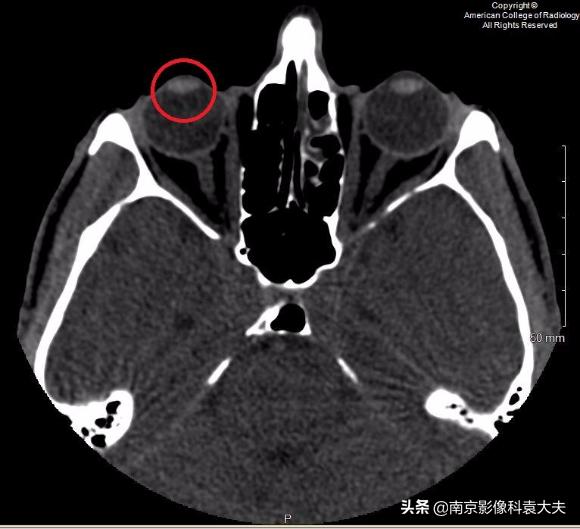

上图 在晶状体水平轴位非对比CT图像显示右眼前房(圆环)前后径减小,临床上可在角膜裂伤的情况下看到。

穿透性创伤或裂伤可能损害前房,使虹膜脱出进入前房。在CT图像上,前房液体的体积减少导致前房的前后径缩小。